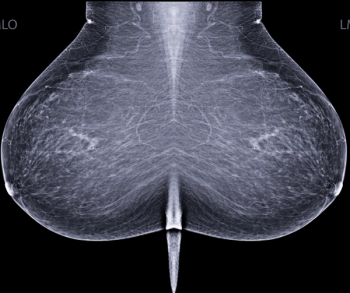

In separate test sets of Israeli women and United States women who had either ductal carcinoma in situ or invasive breast cancer, emerging artificial intelligence (AI) algorithms achieved an area under the curve (AOC) of 88 percent and 80 percent, respectively, for malignancy detection.